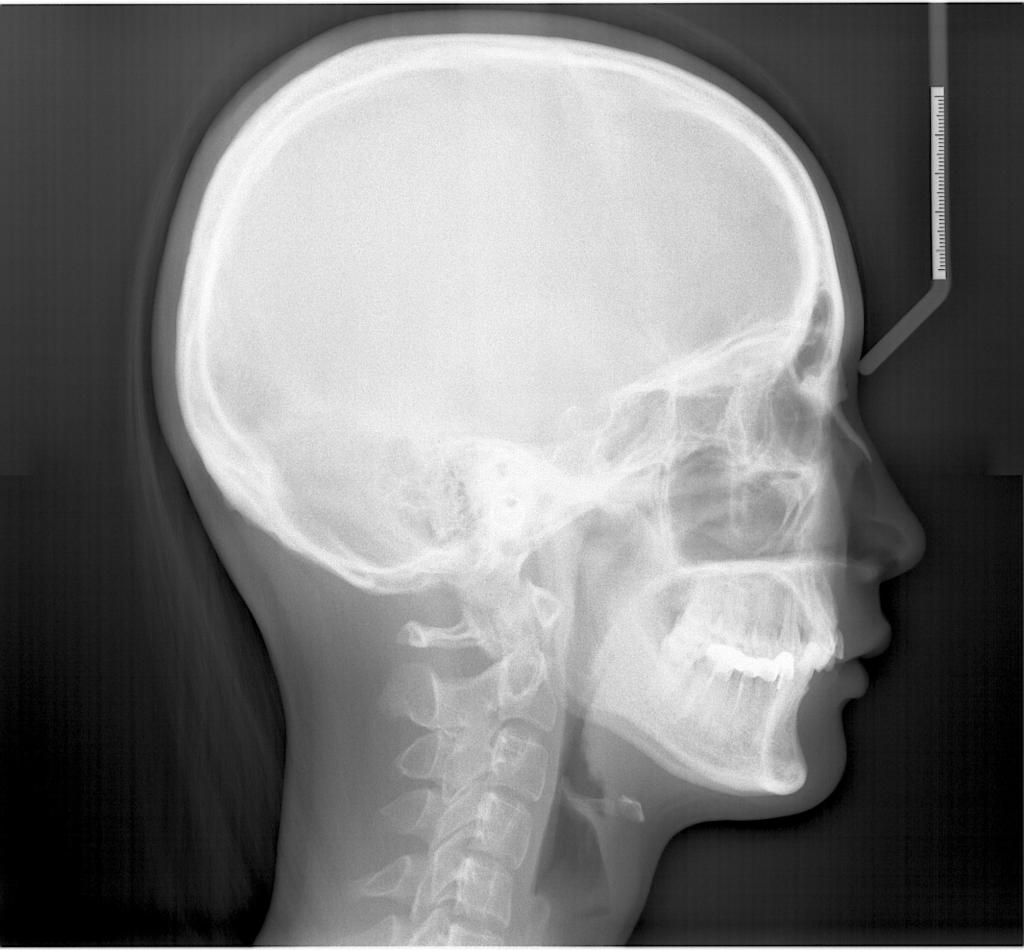

头影测量侧位/正位片

诊断范围涉及牙体牙髓病、牙周病、阻生牙/多生牙定位、种植牙术前CT评估分析、颞下颌关节CT诊断分析、,颌骨及涎腺疾病、颌面发育畸形、正畸治疗辅助诊断等大部分颌面部疾病,为临床医疗提供强有力的支持。